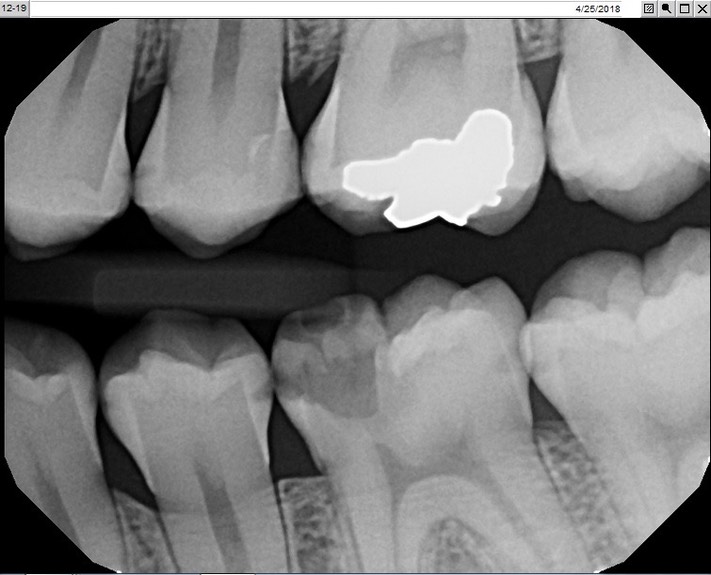

Kris Nip #19